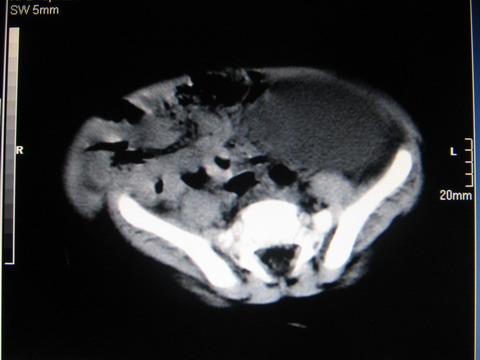

标题: PED0552:男1岁,双肾区CT [打印本页]

标题: PED0552:男1岁,双肾区CT

胎龄5个月时b超示左肾积水,现一岁后复查

左肾盂积水.先天性左输尿管狭窄?

左肾重度积水(先天性左输尿管狭窄所致?)。

先天性左输尿管狭窄所致左肾重度积水。